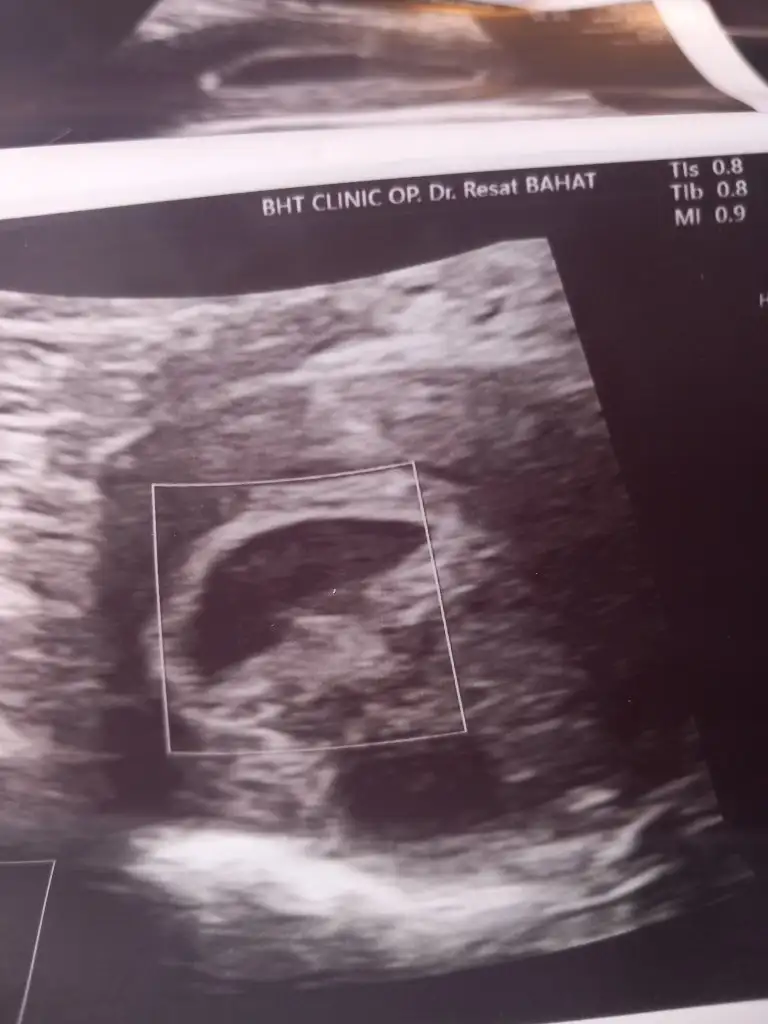

Doktor bisey demedi 6 gun sonrasi için gun verdi. Ben ileri yas hamileligi yaşıyorumMerhaba bende yarın 6 haftalik oluyorum. 6+4 de gitmeyi düşünüyorum. Dr ne dedi duyduğuma göre yolk iyi bisey mis sonraki günlerde bebek oluşacak mis.

BEN 6+1 DE GİTMİŞTİM KESE VE YOLK GÖZÜKTÜ KESE 14MM Dİ SONRA 7+4 DE GİTTİM ADET TARİHİME GÖRE BEBEK VE KALP ATIŞI GÖZÜKTÜ GEBELİĞİM 6+4 GÜNDÜ GERİDEN GELİYORMUŞ BİR HAFTA KESE BOYU KAÇMerhabalar 6+2 haftalik hamileyim. Yolk kesesini gördük yanliz kalp atışını alamadık normal mi? Ekte ultrasyon goruntulerim var. Yolk kesesini siz de gördünüz mü?

Normal. Saglikla gelsin insallah, omru guzel olsun.Merhabalar 6+2 haftalik hamileyim. Yolk kesesini gördük yanliz kalp atışını alamadık normal mi? Ekte ultrasyon goruntulerim var. Yolk kesesini siz de gördünüz mü?

Benim kesemin haftasiyla uyumlu olduğunu söyledi doktorum. Kalp atisi almam gerekiyordu alamadım dediBEN 6+1 DE GİTMİŞTİM KESE VE YOLK GÖZÜKTÜ KESE 14MM Dİ SONRA 7+4 DE GİTTİM ADET TARİHİME GÖRE BEBEK VE KALP ATIŞI GÖZÜKTÜ GEBELİĞİM 6+4 GÜNDÜ GERİDEN GELİYORMUŞ BİR HAFTA KESE BOYU KAÇ

yolksac gözüktüyse bi kaç güne bebekte gözükür kuzumBenim kesemin haftasiyla uyumlu olduğunu söyledi doktorum. Kalp atisi almam gerekiyordu alamadım dedi

Yolk kesesi var dedi doktorsanırım yolksacta gözükmüyor canım

Vajinal ultrasonlamı baktı benimde ilk yolk gözüktü sonraki hafta bebek ve kalp atışıYolk kesesi var dedi doktor

Hem vajinal hemde karından. Bakan kişi perinatolog aynı zamandaVajinal ultrasonlamı baktı benimde ilk yolk gözüktü sonraki hafta bebek ve kalp atışı

evet reşat hocanın ismini çok duydum iyi bi doktormuşHem vajinal hemde karından. Bakan kişi perinatolog aynı zamanda

Benim zuat acar Reşat beyin odasında vajinal baktıevet reşat hocanın ismini çok duydum iyi bi doktormuş